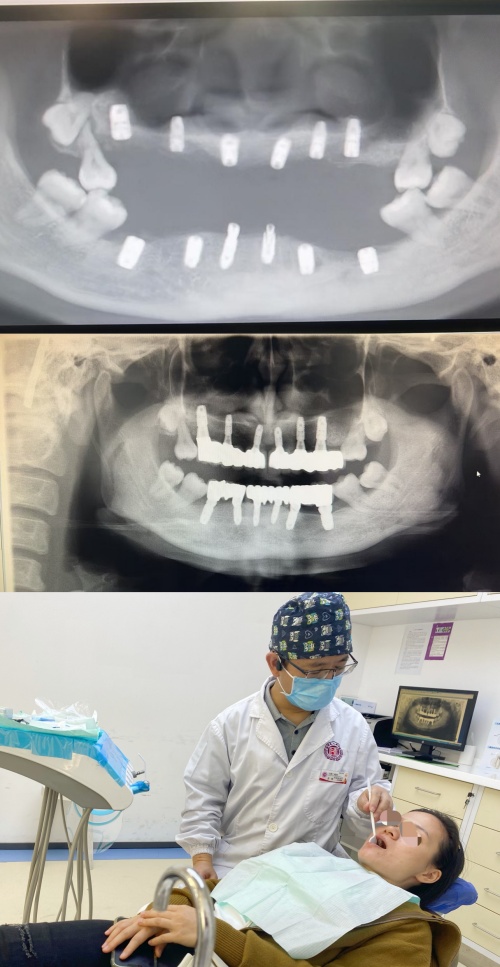

接诊的张特主任检查发现,让朱女士30岁的年龄却有80岁的牙齿的罪魁祸首是侵袭性牙周炎,于是待其牙周状况稳定后,为她做了全口种植修复,3个月后,朱女士戴上了“新牙”,颜值大大提升,绽放出自信笑容。12月18日,朱女士复诊后对诊疗效果赞不绝口,对张特主任团队表示感谢。

牙周炎分慢性与侵袭性两种。侵袭性牙周炎也曾被称为青少年牙周炎、快速进展性牙周炎和青春前期牙周炎。张特主任表示,侵袭性牙周炎是发生在全身健康的年轻人、疾病进展快速、有家族聚集性的一类牙周炎,也称为青少年牙周炎、快速进展性牙周炎。侵袭性牙周炎最大的特点是发病年龄早、疾病进展快,甚至有在11、12岁就出现牙齿松动移位甚至脱落的情况。病变发展迅速,已致发病早期牙齿就出现松动、移位、牙周袋形成,然后出现继发感染。